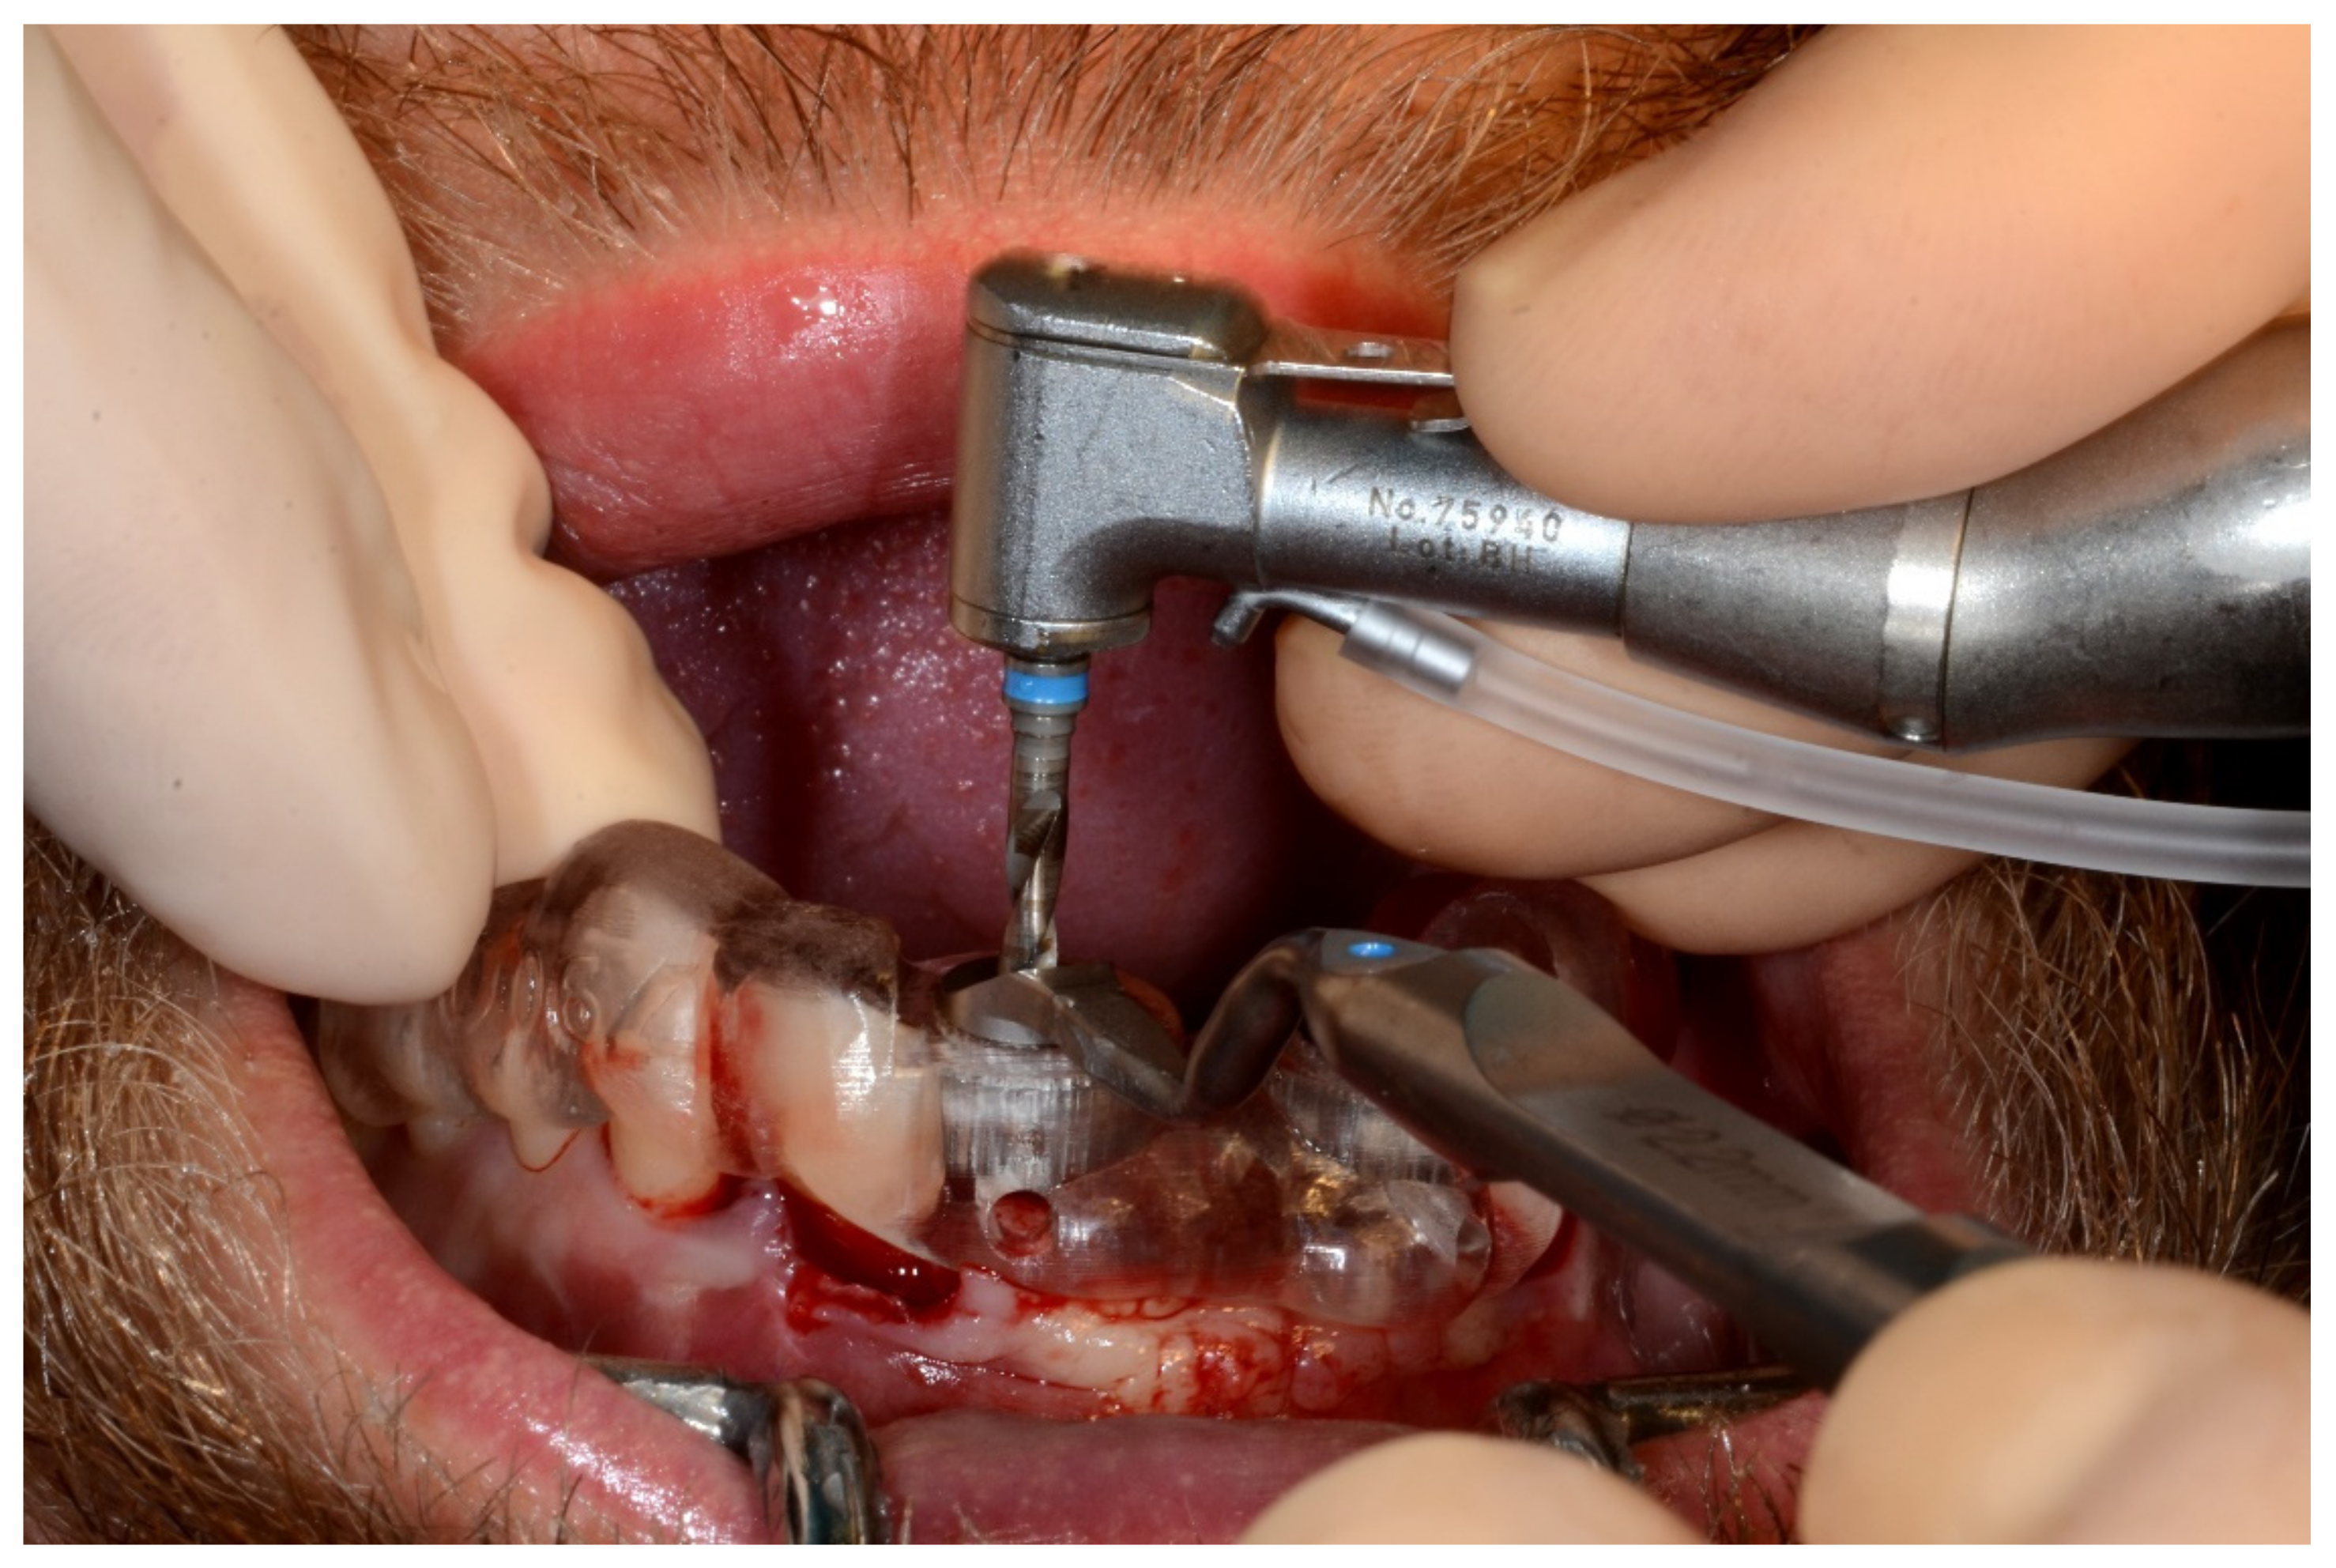

Figure 8.

Implant bed preparation by using guided drills inserted into specific ad hoc drill handles.

In November 2017, two guided dental implants were placed at sites # 12 and # 21 (Figure 7, Figure 8, Figure 9, Figure 10 and Figure 11).